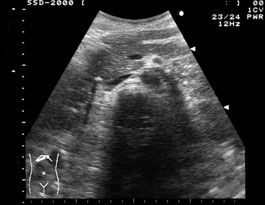

総胆管結石は、胆石と同様の音響陰影を伴う強エコーとして描出されれば典型的であるが、音響陰影に乏しいことやあまり強エコーに描出されないこともある。 |

拡張した胆管を下流に向けて長軸方向に追うと,膵内胆管の中に結石を確認できた. |